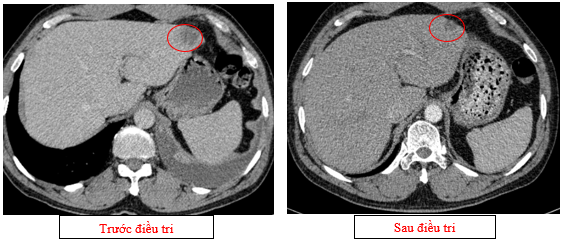

-         Chụp cắt lớp vi tính ổ bụng (08/2025): Nhu mô gan phải có vài nốt, nốt lớn nhất hạ phân thùy VII có nốt giảm tỷ trọng, ngấm thuốc kém sau tiêm đường kính 24mm, hạ phân thùy II, III có nốt 2 giảm tỷ trọng đường kính 13mm và 27mm. Các ổ đặc xương rải rác đốt sống ngực thắt lưng, xương cùng và xương chậu hai bên – theo dõi tổn thương thứ phát

Hình 04: Nhu mô gan phải có vài nốt, nốt lớn nhất hạ phân thùy VII có nốt giảm tỷ trọng, ngấm thuốc kém sau tiêm đường kính 24mm, hạ phân thùy II, III có nốt 2 giảm tỷ trọng đường kính 13mm và 27mm

-         Chụp cắt lớp vi tính ổ bụng (11/2025): Nhu mô gan phải có vài nốt, nốt lớn nhất hạ phân thùy VII có nốt giảm tỷ trọng, ngấm thuốc kém sau tiêm đường kính 8mm, hạ phân thùy II, III có nốt giảm tỷ trọng đường kính (tổn thương giảm đáng kể so với phim chụp ngày 08/2025). Các ổ đặc xương rải rác đốt sống ngực thắt lưng, xương cùng và xương chậu hai bên.

Hình 11: Tổn thương ngấm thuốc kém nhu mô gan hạ phân thùy II giảm đáng kể kích thước

Hình 12: Tổn thương ngấm thuốc kém nhu mô gan hạ phân thùy VII giảm đáng kể kích thước

+      Các tổn thương ngấm thuốc kém do di căn tại gan giảm kích thước đáng kể (27mm còn 8mm)